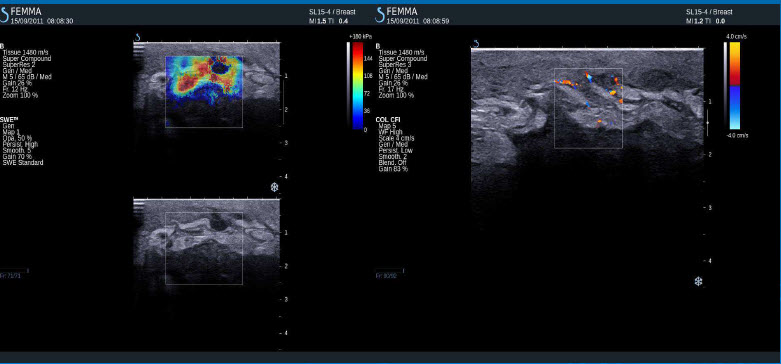

Pozitivní výsledky elastografie / histologicky potvrzená malignita

Invazivní duktální adenokarcinom